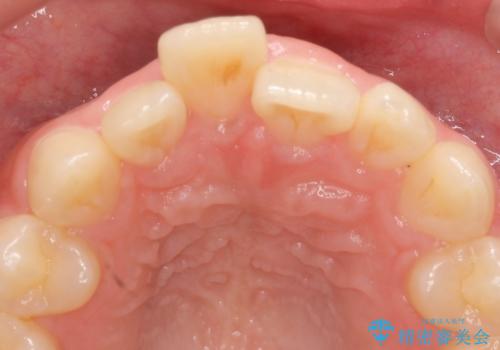

- 前歯の突出を主訴に来院。

矯正治療は絶対したくないとのことでした。

矯正治療をするメリット(神経を取らずに済む、歯を削らずに済む、セラミックを入れずに済む、歯ぐきのラインが整う)をお話しましたが、希望されませんでした。

部分矯正なども提示しましたが、早く治すセラミック治療を選択されました。

前歯の角度や歯ぐきのラインに差が大きかったため、やむなく神経をとり、歯ぐきの手術を行い出来るだけ歯ぐきのラインを整えるようにしました。

手術をしなければ左上1番の歯ぐきのラインは左上2番よりも下にきてしまい、長さの短い歯になってしまうところでした。